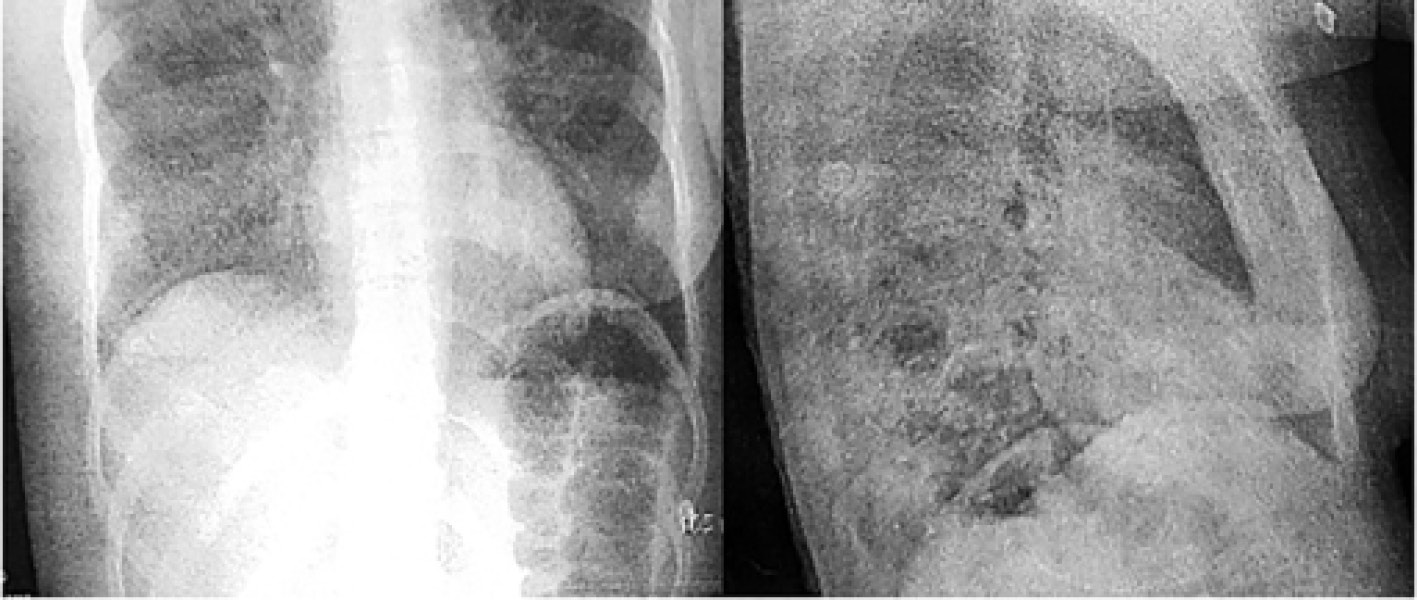

На четвертые сутки с помощью проведения трансфузий свежезамороженной плазмы купированы проявления геморрагического синдрома, нарушения гемостаза (см. рис. 3). Для исключения дополнительной причины анемии и исключения кровотечения выполнена фиброэзофагогастродуоденоскопия (ФЭГДС), были выявлены множественные эрозии слизистой желудка, данных за кровотечение не получено. По результатам ФЭГДС проконсультирована хирургом, который установил диагноз: «Эрозивно-катаральный гастрит. Состоявшееся желудочно-кишечное кровотечение. Гемостаз устойчивый». На рентгенограмме органов грудной клетки по-прежнему сохранялись инфильтративные изменения в обоих легких. В ходе выполнения ультразвукового исследования (УЗИ) органов брюшной полости выявлены признаки деформации желчного пузыря, а также диффузные изменения паренхимы обеих почек, в связи с чем проведен осмотр нефрологом, который установил, что гиперазотемия не имеет критического характера и показаний к заместительной почечной терапии нет.

На семнадцатые сутки состояние пациентки оценивалось ближе к удовлетворительному, сознание сохранялось ясным, гемодинамика была стабильной, дыхание самостоятельным и эффективным, кроме того, рентгенологически было отмечено разрешение очагов пневмонической инфильтрации (рис. 8).

Рис. 8. Рентгенограмма органов грудной клетки при выписке